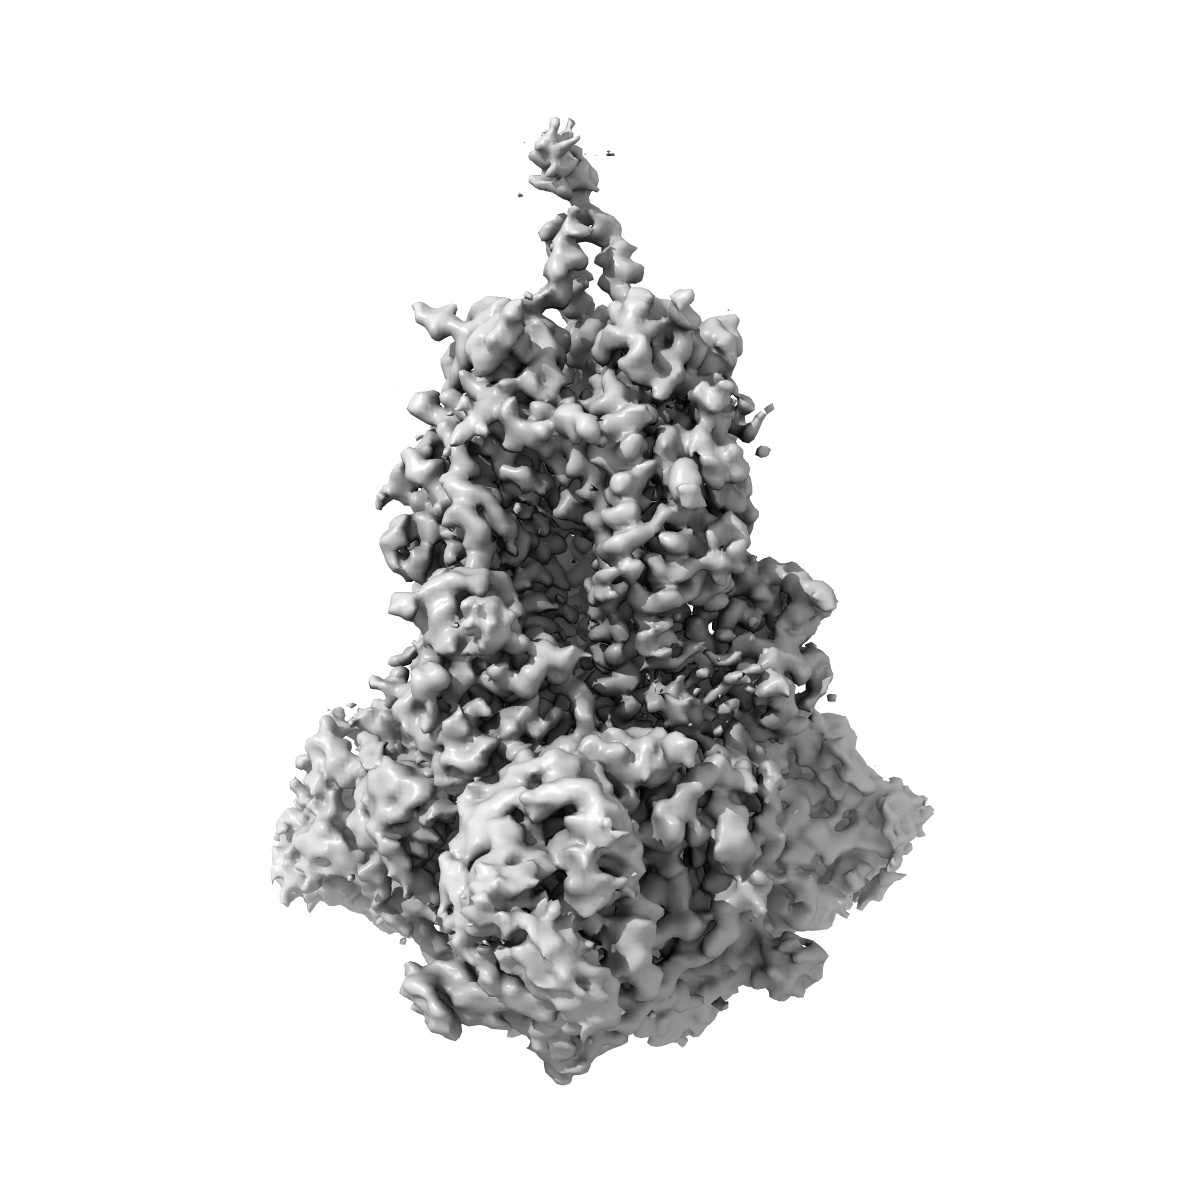

Delta (B.1.617.2) SARS-CoV-2 variant spike protein (S-GSAS-Delta) in the 3-RBD-down conformation; Subclassification D8 state

Single-particle3.57 Å

Sample: Delta (B.1.617.2) SARS-CoV-2 variant spike protein (S-GSAS-Delta) in the 3-RBD-down conformation; Subclassification D8 state

Structural diversity of the SARS-CoV-2 Omicron spike.

(2022) Mol Cell , 82 , 2050 - 2068.e6